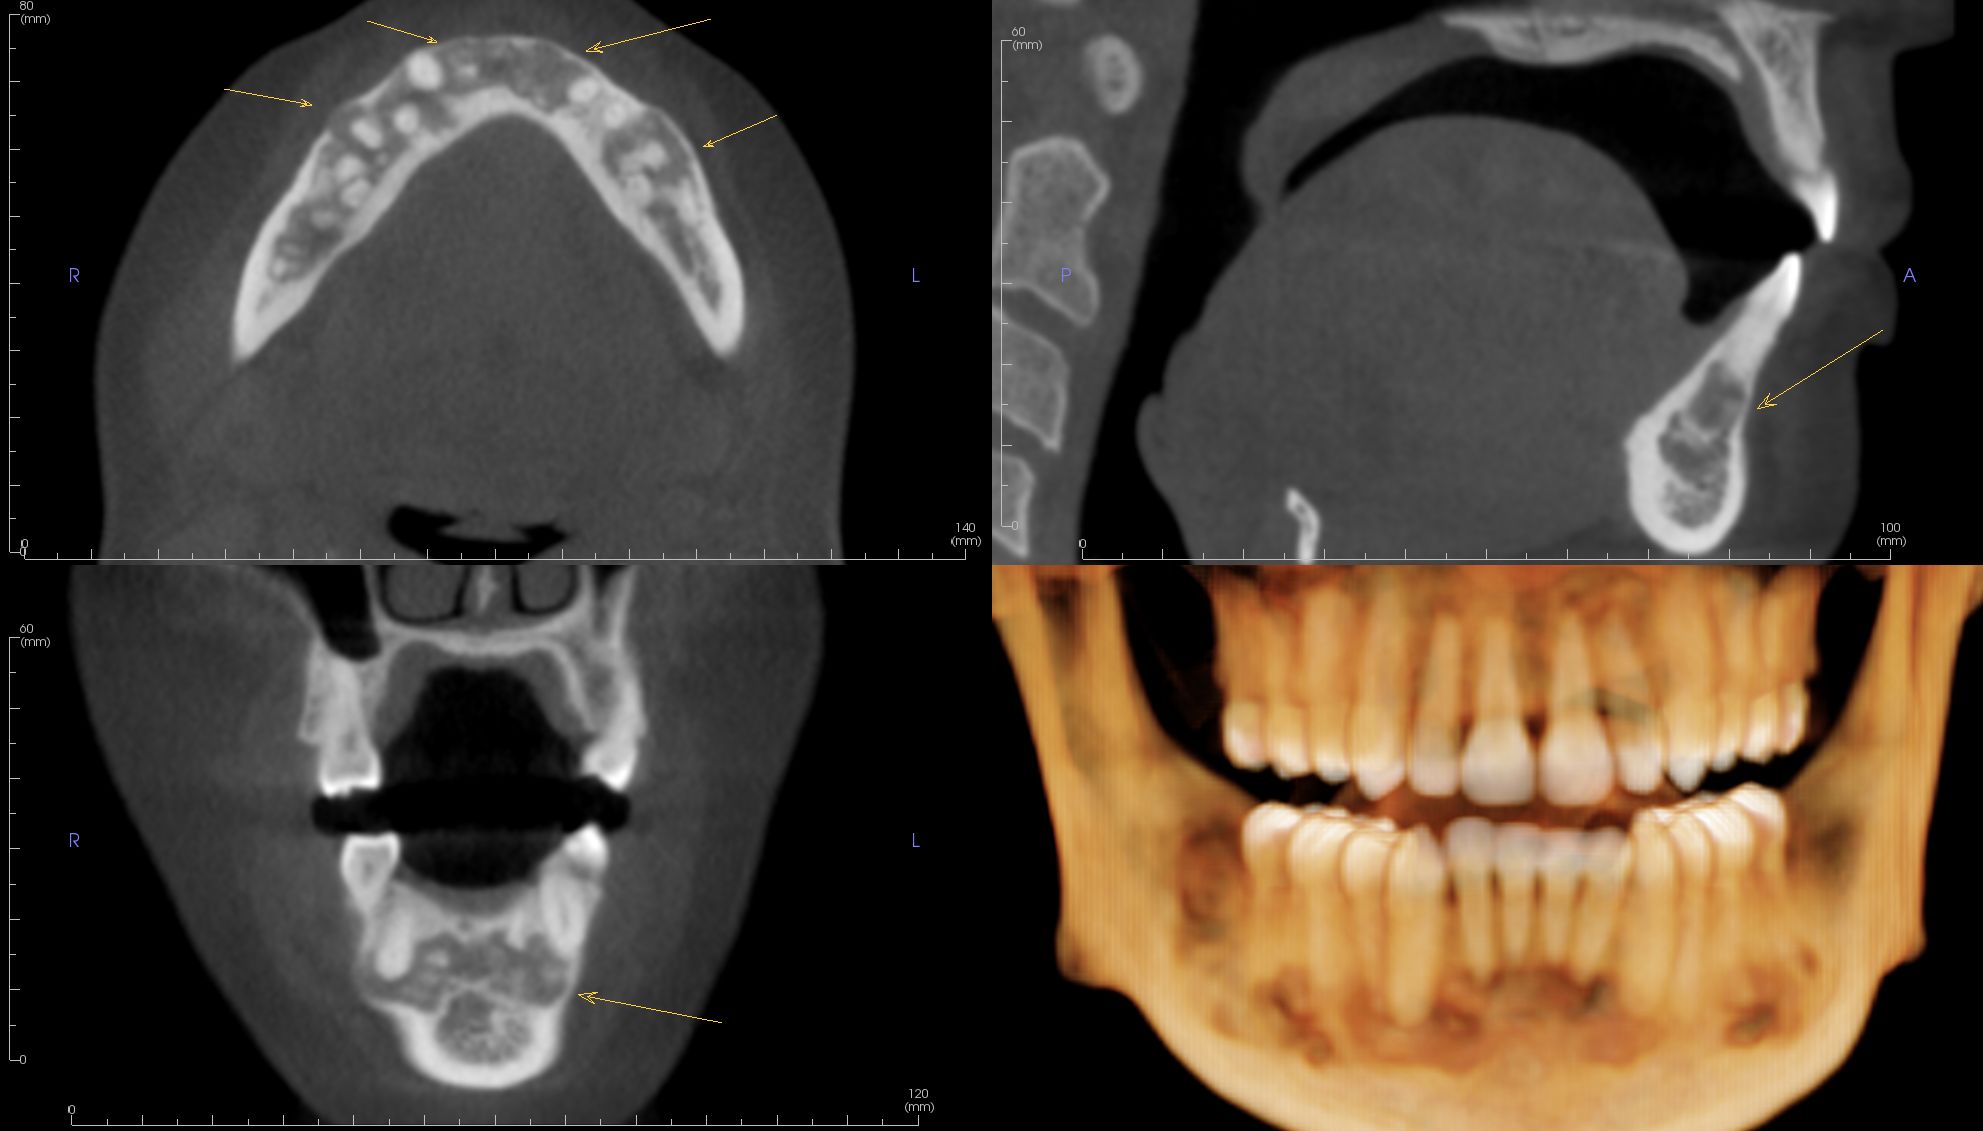

Image Portfolios visually communicate the imaging goals to you and your patient.